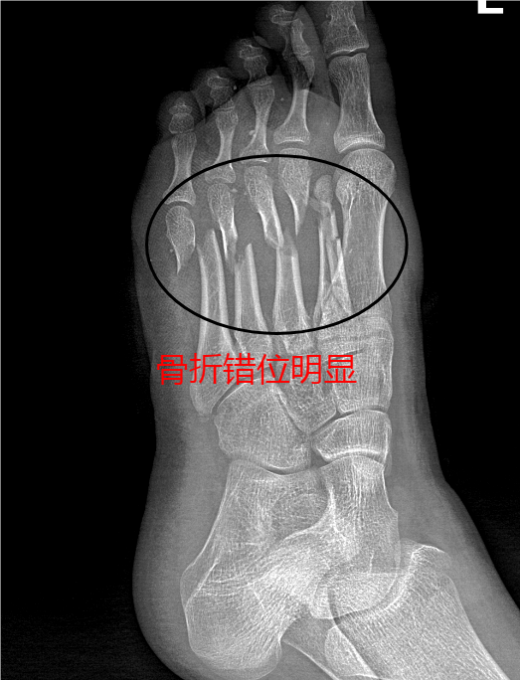

病案简要:患者因“砖块砸伤左足,疼痛、流血、活动受限1小时余。”入院。完善左足DR示:1、左足第3-5跖骨中段骨折。2、左足第2跖骨粉碎性骨折。以“左足开放性损伤伴多发骨折”收入我科 。门诊处查看创口:左足见约10cm不规则创口,深达筋膜层,创面内异物残留,左足肿胀明显,皮肤剥脱,触压痛,活动稍受限,远端足趾肤色正常,感觉稍差。初步诊断:1、左足部开放性损伤伴骨折(左足开放性2、3、4、5跖骨骨折);2、左足皮肤部分剥脱;3、左足软组织损伤并异物残留。入院后完善相关检查后行急诊手术,术后修整皮瓣,予VSD负压吸引,两个疗程后打开VSD见新生皮肤生长,剥脱皮肤成活80%以上,术口无任何感染。